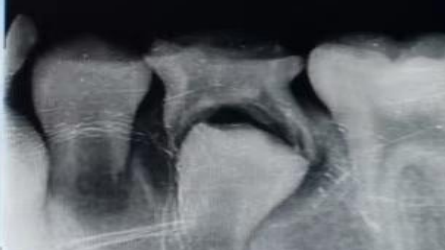

乳牙根尖周病的特点

1. 乳牙根尖周病早期症状不明显,往往出现急性炎症时就诊。

2. 慢性炎症为主,急性根尖周炎多是慢性根尖周炎急性发作引起。

3. 患牙松动并有叩痛。

4. 牙龈出现瘘管,反复溢脓肿胀。

5. 乳牙牙周组织疏松,脓液容易从龈沟排出。

6. X线片急性根尖周炎时X线片根尖部无明显。

7. 乳牙根尖周病可以加速牙根吸收。